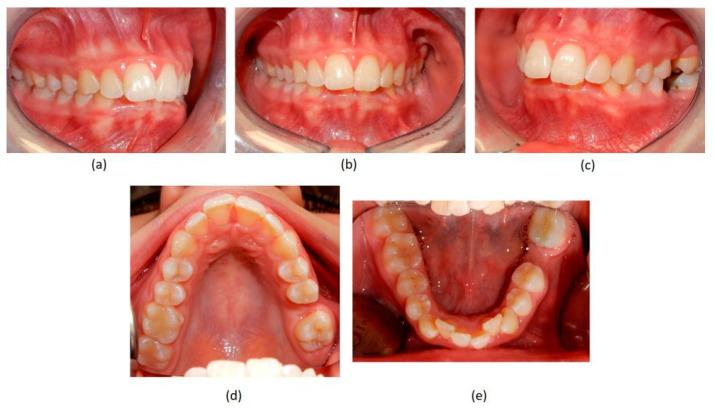

Successful closure of edentulous spaces with clear aligners (CAs) is influenced by many factors. CAs are tailored orthodontic devices whose predictability may have relevant medico-legal implications. This study presents a scoping review about missing molar space closure (MMSC) with CAs and a clinical case. This study aims to highlight the feasibility of molar space closure by mesialization with CAs without hybrid supports. Following PRISMA Sc-review guidelines, English-written randomized/non-randomized/observational clinical studies on PubMed, Scopus, Cochrane and Lilacs were searched. An 18-year-old patient, with upper and lower edentulous spaces due to the loss of two first molars, was rehabilitated with CAs (Sorridi, Sorridi srl, Latina, Italy) without hybrid supports and attachments. The therapy was carried out over 10 months. Currently, there are no studies documenting MMSC by mesialization with only CAs. Existing articles document the closure of premolar or incisor spaces. The upper and lower left second molars replaced the missing first molars, and erupting third molars replaced adjacent teeth. The biomechanical effects in space closure with CAs related to extraction cases appear as priorities of clinical/medico-legal interest. Our case turns attention to this movement of CAs without attachments/hybrid supports, indicating that even such a complex treatment can be comfortable for patients and safely predictable for specialists.

使用透明矫治器(CA)成功关闭无牙间隙受多种因素影响。CA是定制的正畸装置,其可预测性可能具有相关的医疗法律意义。本研究呈现了一项关于使用CA关闭缺失磨牙间隙(MMSC)的范围综述及一个临床病例。本研究旨在强调在无混合支持的情况下通过CA近中移动关闭磨牙间隙的可行性。遵循PRISMA范围综述指南,检索了PubMed、Scopus、Cochrane和Lilacs上英文撰写的随机/非随机/观察性临床研究。一名18岁患者因两颗第一磨牙缺失导致上下无牙间隙,使用CA(Sorridi,Sorridi srl,拉蒂纳,意大利)进行修复,无混合支持和附件。治疗持续了10个月。目前,尚无研究记录仅通过CA近中移动关闭MMSC的情况。现有文章记录了前磨牙或切牙间隙的关闭。上下颌左侧第二磨牙替代了缺失的第一磨牙,萌出的第三磨牙替代了相邻牙齿。与拔牙病例相关的CA关闭间隙的生物力学效应似乎是临床/医疗法律关注的重点。我们的病例将注意力转向了无附件/混合支持的CA这种移动方式,表明即使是如此复杂的治疗对患者来说也可以是舒适的,对专家来说也可以是安全可预测的。